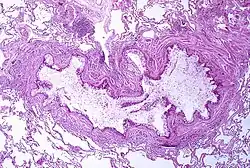

Asthma is the result of chronic inflammation of the conducting zone of the airways (most especially the bronchi and bronchioles), which subsequently results in increased contractability of the surrounding smooth muscles. This among other factors leads to bouts of narrowing of the airway and the classic symptoms of wheezing. The narrowing is typically reversible with or without treatment. Occasionally the airways themselves change.[15] Typical changes in the airways include an increase in eosinophils and thickening of the lamina reticularis. Chronically the airways' smooth muscle may increase in size along with an increase in the numbers of mucous glands. Other cell types involved include: T lymphocytes, macrophages, and neutrophils. There may also be involvement of other components of the immune system including: cytokines, chemokines, histamine, and leukotrienes among others.[11]